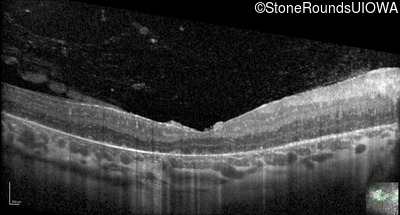

Optical Coherence Tomography - Right - 20/160

Exemplar / OCT Stack

OCT Stack